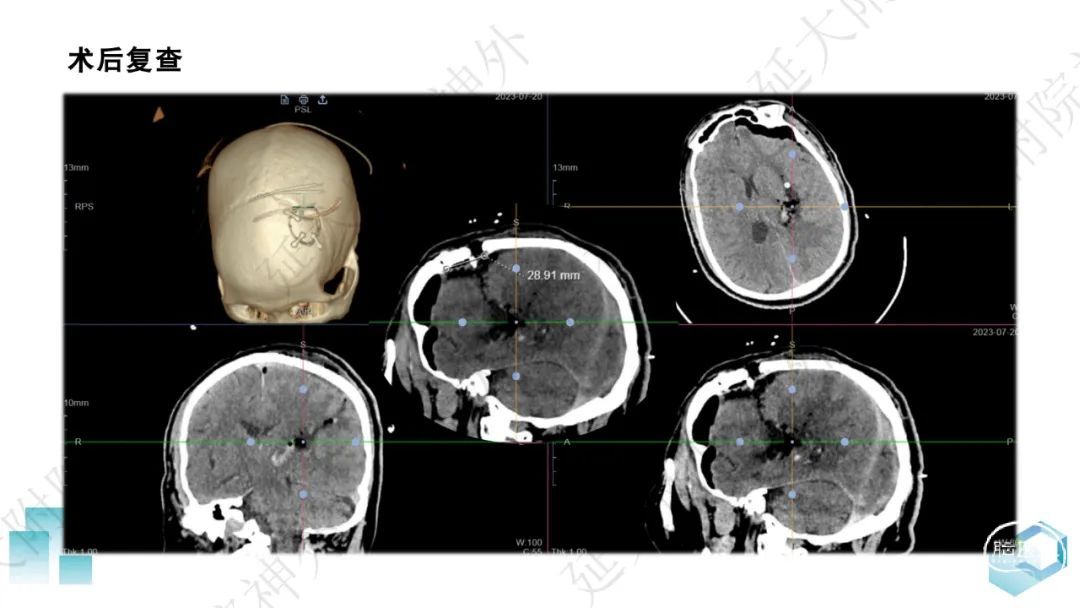

今天为大家分享的是《监测有道丨颅脑创伤-神经重症周刊》第332期,由延安大学附属医院神经外科贾云峰主任医师带来的:左侧基底节区出血破入脑室一例神经内镜下血肿清除术,欢迎阅读、分享。